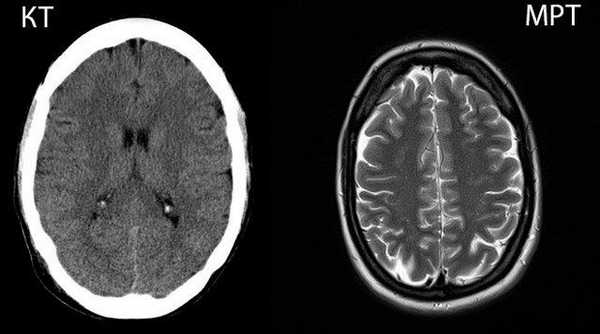

КТ и МРТ: в чем отличия и что лучше?

Компьютерная и магнитно-резонансная томографии — это современные информативные диагностические процедуры, которые позволяют с высокой степенью точности и детализации визуализировать внутренние структуры организма. Оба метода предполагают получение послойных снимков интересующей зоны в разных плоскостях. Основное, чем отличается КТ от МРТ - это принцип сканирования. Методы основаны на разных технологиях и применяются в различных клинических ситуациях. Исходя из задач диагностики, лечащий врач определяет, что лучше — КТ или МРТ, а затем назначает наиболее рациональный метод диагностики для конкретного случая.

Принцип действия КТ и МРТ: в чем разница

Компьютерная и магнитно-резонансная томография относятся к лучевым методам диагностики. Основное отличие КТ от МРТ заключается в технологии воздействия на организм с целью получения изображения.

Компьютерная томография использует ионизирующее излучение (рентген-сканирование). Метод базируется на способности тканей организма в различной мере задерживать рентгеновские лучи. При прохождении сквозь интересующую область лучи максимально поглощаются плотными тканями (например, костями) и легко проникают сквозь мягкотканные элементы. В результате на снимках хорошо визуализируются кости и другие плотные структуры - конкременты, инородные тела.

Отличие компьютерной томографии от стандартной рентгенографии — в количестве получаемых снимков. В ходе КТ вокруг пациента вращается трубка, которая посылает лучи, а специальные датчики их улавливают. В результате процедуры получают пошаговые рентгеновские снимки зоны исследования. Чем чаще вращается трубка, тем меньше шаг сканирования, и, соответственно, выше разрешающая способность.

МР-томография базируется на явлении ядерно-магнитного резонанса, свойственного атомам водорода, содержащимся в молекулах воды. Больше всего воды присутствует в мягких тканях. Ткани, которые содержат мало воды (например, кости), визуализируются плохо. Датчик томографа регистрирует изменения состояния атомов водорода под воздействием радиоизлучения в постоянном магнитном поле.

В результате получают пошаговые снимки в трех плоскостях, на которых видны мягкотканные структуры организма.

Понимая, в чем состоит разница между КТ и МРТ, можно сделать логический вывод о большей информативности процедуры относительно тех или иных видов тканей. Однако диагностические возможности методов можно расширить с помощью контрастных веществ. При КТ применяют йодсодержащий контраст, который распределяется в организме с током крови и делает видимыми сосуды и некоторые мягкие ткани. Это позволяет в ряде случаев применять КТ для исследования внутренних органов, новообразований и сосудов.